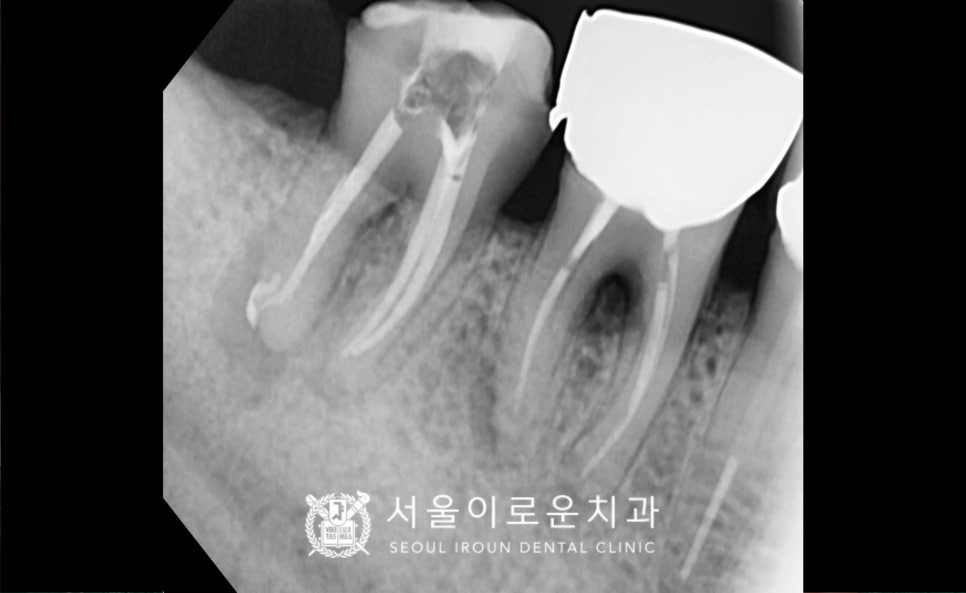

아래턱 오른쪽 두 번째 큰 어금니(#47)의

치료도 진행하였는데요.

치료를 위해 기존 크라운을 제거하고

충치를 깔끔하게 제거 후

뿌리 끝까지 신경치료를

꼼꼼하게 마무리 해드렸답니다.

신경치료 후 기존 증.상들이

사라지신 것을 확인한 후

크라운 수복을 위한 인상채득 후

위턱과 마찬가지로 지르코니아 보철물로

수복을 마무리해 드렸습니다.